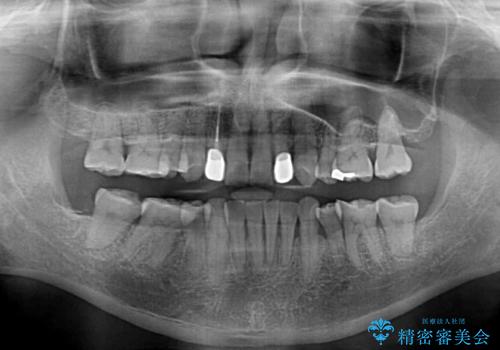

- 骨格的な咬み合わせのズレ、前歯のデコボコとクロスバイトを気にして来院された患者様です。

全額的にデコボコが強いため、上下左右の小臼歯計4歯を抜歯し、ワイヤー装置による矯正治療を行うこととしました。

抜歯する歯の一部をセオリーである第一小臼歯ではなく、第二小臼歯にすることで、骨格的なずれをカバーするように計画しました。

小臼歯の抜歯する部位を選択したことで、安定した咬み合わせとなりましたが、第二小臼歯を抜歯した部分はスペースを閉じるのに長い期間を要しました。

矮小歯であった上顎前歯2本は、矯正治療後にバランスの取れた大きさのオールセラミッククラウンを装着しました。